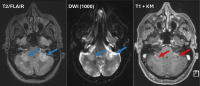

Abbildung 4: Patient B: cMRT von Mai 2022 (FLAIR-Sequenz, DWI-Sequenz, T1-Sequenz mit KM): neu aufgetretene Kleinhirnläsion links (blauer Pfeil) mit Diffusionsrestriktion (grüner Pfeil), fleckig inhomogene KM-Speicherung der Läsion („milky way sign“, roter Pfeil)